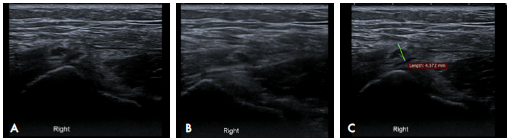

The patient underwent multiple analgesic (until being prescribed with hydrocodone + acetaminophen, which she takes irregularly) and anti-inflammatory treatments, and received multiple physiotherapy sessions without improvement; in fact, her symptoms increased progressively. After assessment by Orthopedics, she was diagnosed with bilateral snapping hip syndrome, with retraction of the tensor fasciae latae. An ultrasound of the hip was performed on both sides, finding thickening of the right tensor fasciae latae (4mm), alteration of the fibrillary pattern and tendon protrusion over the greater trochanter during dynamic assessment, accompanied by an audible and palpable "snap" (Figure 2) (Video 1). Magnetic resonance imaging (MRI) of the hip showed bilateral edema of the ITB and slight thickening of the ITB on the right side (2.3mm) (Figure 3).

Dynamic ultrasound of the iliotibial band over the greater trochanter. A) neutral position of the right hip; B) hip internal rotation; C) thickening of the iliotibial band measured in the transverse plane associated with heterogeneous echogenicity of the tendon.

Figure 2: Dynamic ultrasound of the iliotibial band over the greater trochanter. A) neutral position of the right hip; B) hip internal rotation; C) thickening of the iliotibial band measured in the transverse plane associated with heterogeneous echogenicity of the tendon.

Source: Document obtained during the study.